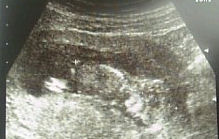

4カ月(12週と3日)になりました。今日は待ちに待った検診の日。4週間はホントに長く感じられます。特に私はつわりなど全くなく、普通に生活しているので、どうも妊婦の自覚がなく、お腹の中でちゃんと生きてるのかも心配でした。今回から検診は予約制。まず尿検査をしてから、外来へ行きました。うちは、姉が出産で死にかけたことがあるので、設備が整っている総合病院で産もうと思っています。常時先生が二人いて、NICUとかもあるみたいなので。あと、子宮内膜症をずっと診てもらって手術もしている病院なので。総合病院は良い点もあるのですが、待ち時間が長いのがちょっときついですよね。予約時間から30分経ってから呼ばれました。まず、体重と血圧を測りました。体重、すでに生まれそうなぐらい重いのですが・・・(苦)その後に病歴など聞かれ、分娩予約を入れてきました。そしてまた30分ぐらい待たされ、やっと腹部エコー。スカートを少し下ろして、お腹を出し、お腹にジェルを塗ってエコー開始。赤ちゃんの手足がしっかり見えて、顔も分かりました☆今現在5センチ。写真右側が頭で下を向いています。左側にちょろっと見えるのが足です。今回ピクピク動いてるのも見えたのですが、ホントになんか生きてるんだなぁって思うと感動してしまいました。毎回泣けてしまうのですが(笑)と感動の時間はあっというまに過ぎ、診察終了。短かったなぁ。帰りに採血をして帰りました。4本も採られちょっと貧血気味です。今日の会計は9100円。ん??住所地から検査費助成の紙をもらって提出しましたが、助成されて9100円?高くない???疑問を残しつつ支払いし、帰って来ました。弱い私。次回はバースプランを書いて8月16日です。また4週間後。長すぎる~。自分でエコーを買ってしまった人の気持ちが良く分かります(笑)